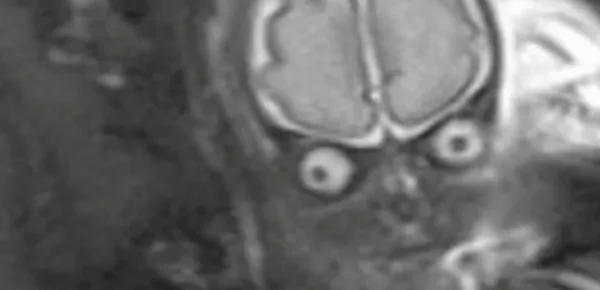

Lo scatto curioso è stato immortalato da una risonanza magnetica su una giovane mamma in attesa di trenta settimane. L'immagine ha lasciato i genitori del piccolo, sconcertati.

Il loro bambino, che sarebbe nato da lì a poco, somigliava in tutto e per tutto a un alieno proveniente da una galassia lontana. Presentava grandi occhi tondi e sporgenti che sembrava fissassero il monitor. Possiamo soltanto immaginare la sorpresa e lo sbigottimento provato dai due giovani papà e mamma. I medici hanno immediatamente rassicurato i due giovani genitori sulle condizioni del feto, ormai giunto alla trentesima settimana. Il bambino non aveva alcun tipo di problematica. Oggi il piccolo Lucas è un bellissimo bambino sano come un pesce senza alcuna caratteristica 'aliena'. I giovani genitori oggi possano raccontare la vicenda sollevati mostrando alle telecamere il loro piccolo Lucas.

Il piccolo a differenza delle immagini ecografiche che siamo abituati a vedere, appariva con caratteristiche molto simili a quelle che nell'immaginario e nella cinematografia rappresentano i marziani. Il piccolo appariva molto simile agli alieni rappresentati da Tim Burton in 'Mars Attack'. Dopo il primo momento di sbigottimento i genitori, rassicurati dai medici che hanno spiegato ai due genitori sconvolti che l'effetto era dovuto all'esame particolare, sono scoppiati a ridere. I medici avevano sottoposto il piccolo nel ventre materno a una risonanza magnetica per assicurarsi che i fosse sano.